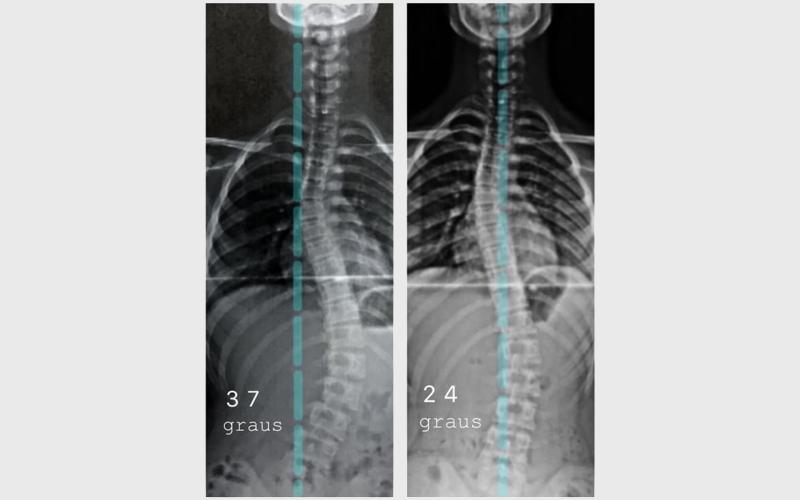

Existem tratamentos não cirúrgicos que podem atrasar a progressão ou até reduzir a Escoliose.